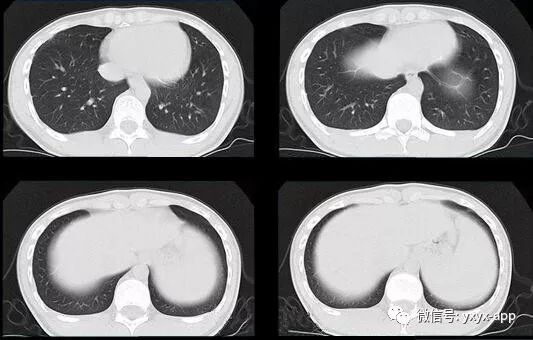

评论:两肺斑片状磨玻璃影,与周围组织分界清楚,呈“地图样”表现,部分病变延伸至胸膜下,部分小叶间隔增厚,气管居中,肺门及纵膈未见肿大淋巴结影,未见胸腔积液。患者青年男性,临床症状轻微影像表现严重,抗炎治疗无效。考虑肺泡蛋白沉积症

1、两肺较淡的斑片状磨玻璃影,不呈叶段分布,病变可延伸至胸膜下,其中磨玻璃影中可见小结节影,磨玻璃影与正常肺组织分界清楚,形成“地图样”改变,这种地图样分布的原因,可能是由于这种斑片影以肺小叶为病变单位,小叶间隔在一定程度上限制了病变的蔓延;

2、由于小叶间隔和小叶内间隔的增厚形成网格状阴影改变,弥漫的磨玻璃影及其内部的网格小叶间隔增厚形成了“铺路石样”改变;